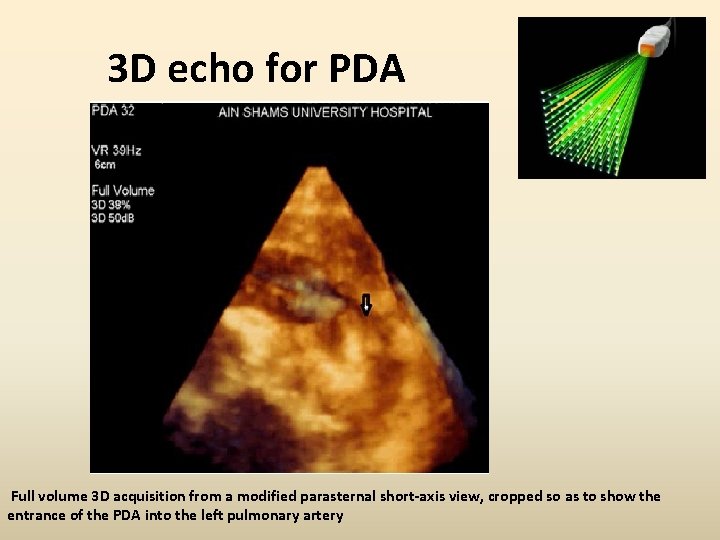

3 D echo for PDA Full volume 3 D acquisition from a modified parasternal short-axis view, cropped so as to show the entrance of the PDA into the left pulmonary artery